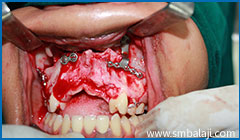

Surgical exposure of lower right impacted teeth

Surgical exposure of lower left impacted teeth